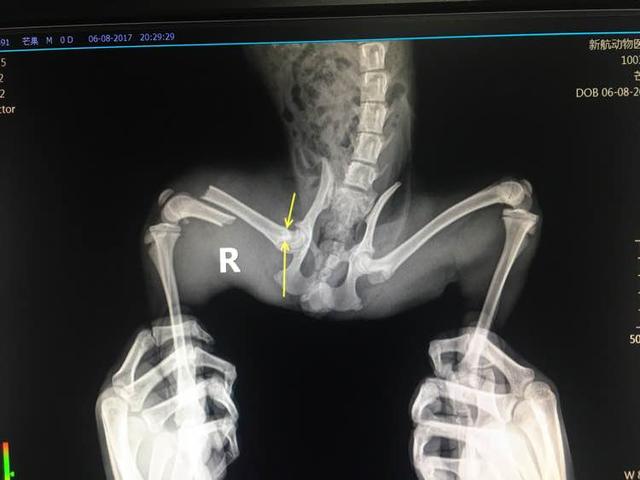

没办法送去了宠物医院,X光一照,发现坏了。腿骨粉碎性骨折。。。。

可能已经疼得麻木了吧,在医生照射X光时,我的双手一直抓着小布丁的腿往两边开,它表现得很乖,没叫也没有挣扎。

我是学生,没有多少钱,要医生做一个外固定,这样应该只要两三千。但医生说这个位置做不了外固定,只能动手术做个内固定,一套治疗下来要花6~7千元。